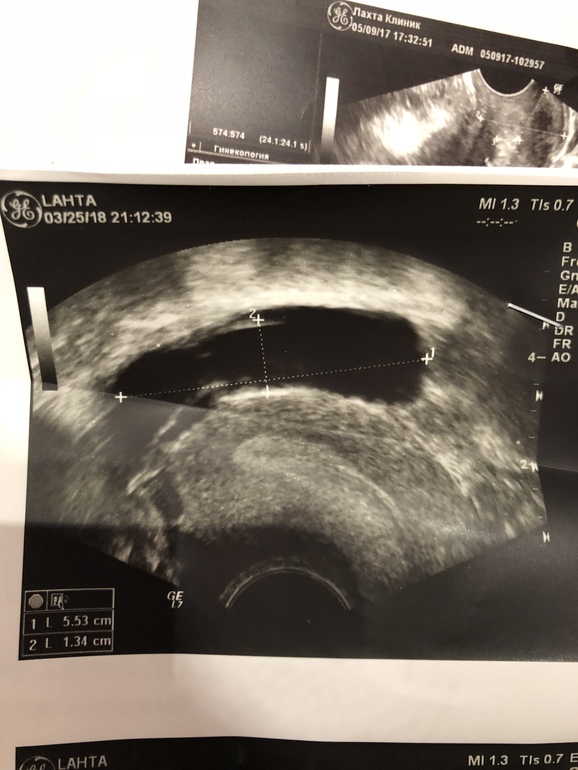

«За маткой, больше справа, рядом с Правым яичником вытянутое образование размерами 52х22 мм с умеренно утолщенными стенками , эхопозитивными перегородками и мелкодисперсной взвесью в структуре содержимого (маточная труба?)»

Предварительный диагноз - гидросальпингс (((((

С перепугу на следующий день (вчера) сходила к ещё одному узисту на другой аппарат - тот же диагноз. (

Вот